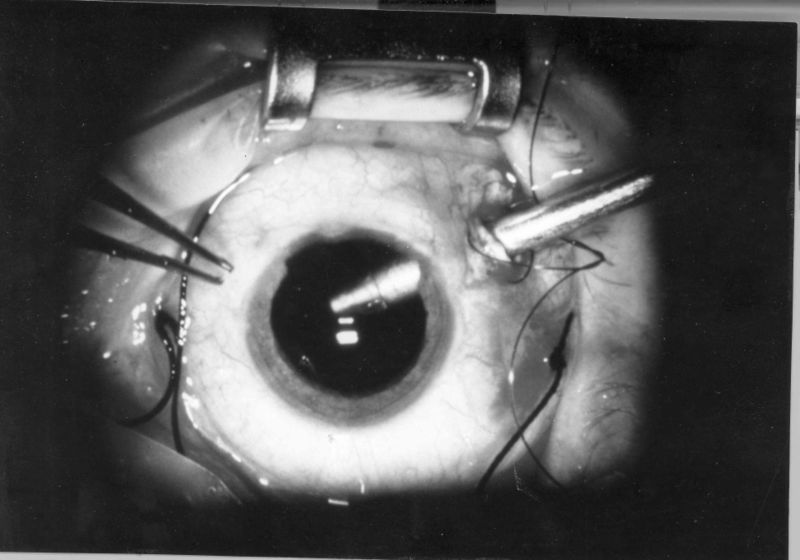

Preparing for a vitreoretinal procedure and understanding recovery.

Read article